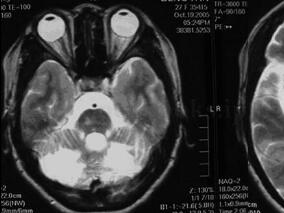

1小时条评论女,27岁。 主诉:发作性意识丧失、抽搐5年,眩晕伴右侧肢体无力20天。 病史:患者5年前无明显诱因于活动中突发意识丧失,无恶心呕吐,无抽搐、大小便失禁,无发热畏寒等,于当地医院行头部CT、MRI检查,发现双侧小脑半球、丘脑、脑干右侧脑梗死,腰穿脑脊液未见异...